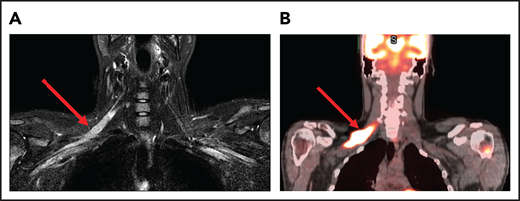

A 24-year-old man presented with stage IVB DLBCL and completed 6 cycles of R-CHOP, with FDG-PET after treatment showing resolution of all disease except in the mediastinum. After a biopsy of this residual FDG+-confirmed DLBCL, he received treatment with salvage chemotherapy with minimal response, followed by mediastinal involved field radiation therapy (IFRT) to a dose of 40 Gy plus a 6-Gy boost, after which he had a CR. Subsequently, he underwent autologous SCT followed by RIC allogeneic SCT. He remained in CR for 16 months, at which time he presented with 3 weeks of new right leg weakness, erectile dysfunction, and urinary hesitancy. The results of a brain MRI were unremarkable, but a spine MRI demonstrated spinal cord expansion and edema with multifocal enhancement within the prior radiation therapy portal from T5 to T9, demarcated by fatty marrow replacement between the T5 and T9 vertebral bodies (Figure 4). A diagnostic evaluation, including CSF analysis, was negative for malignancy, infection, autoimmune or inflammatory conditions, or demyelination. He was diagnosed with radiation-induced myelitis. He was treated with HD-MTX and had a minimal response. Treatment with bevacizumab led to complete resolution of the lesion, and after intensive physical therapy, he regained neurologic function.

MRI of the cervical and thoracic spine of a patient with radiation-induced myelopathy. (A) Axial T1-weighted image after gadolinium contrast shows enhancement within the spinal cord. (B) Sagittal T2 image shows a signal change throughout the patient’s prior radiation portal from T5 to T9, demarcated by fatty marrow replacement between the T5 and T9 vertebral bodies.